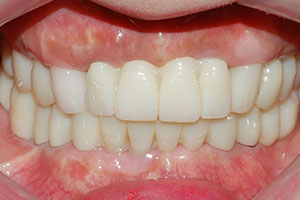

치료증례 전후사진

Before & After